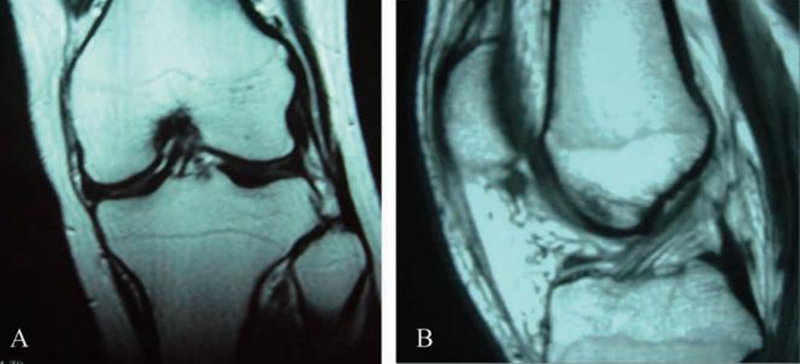

目前为止,双束重建MRI影像学研究还比较匮乏,但ACL的MRI影像显示其有双束或多束结构的并不在少数(图3)。如果韧带断裂,又希望恢复到最佳状态,更优选择应该是能很好地重建其天然结构的解剖双束重建技术(图4)。

图3 ACL的MRI影像 A.双束;B.单束